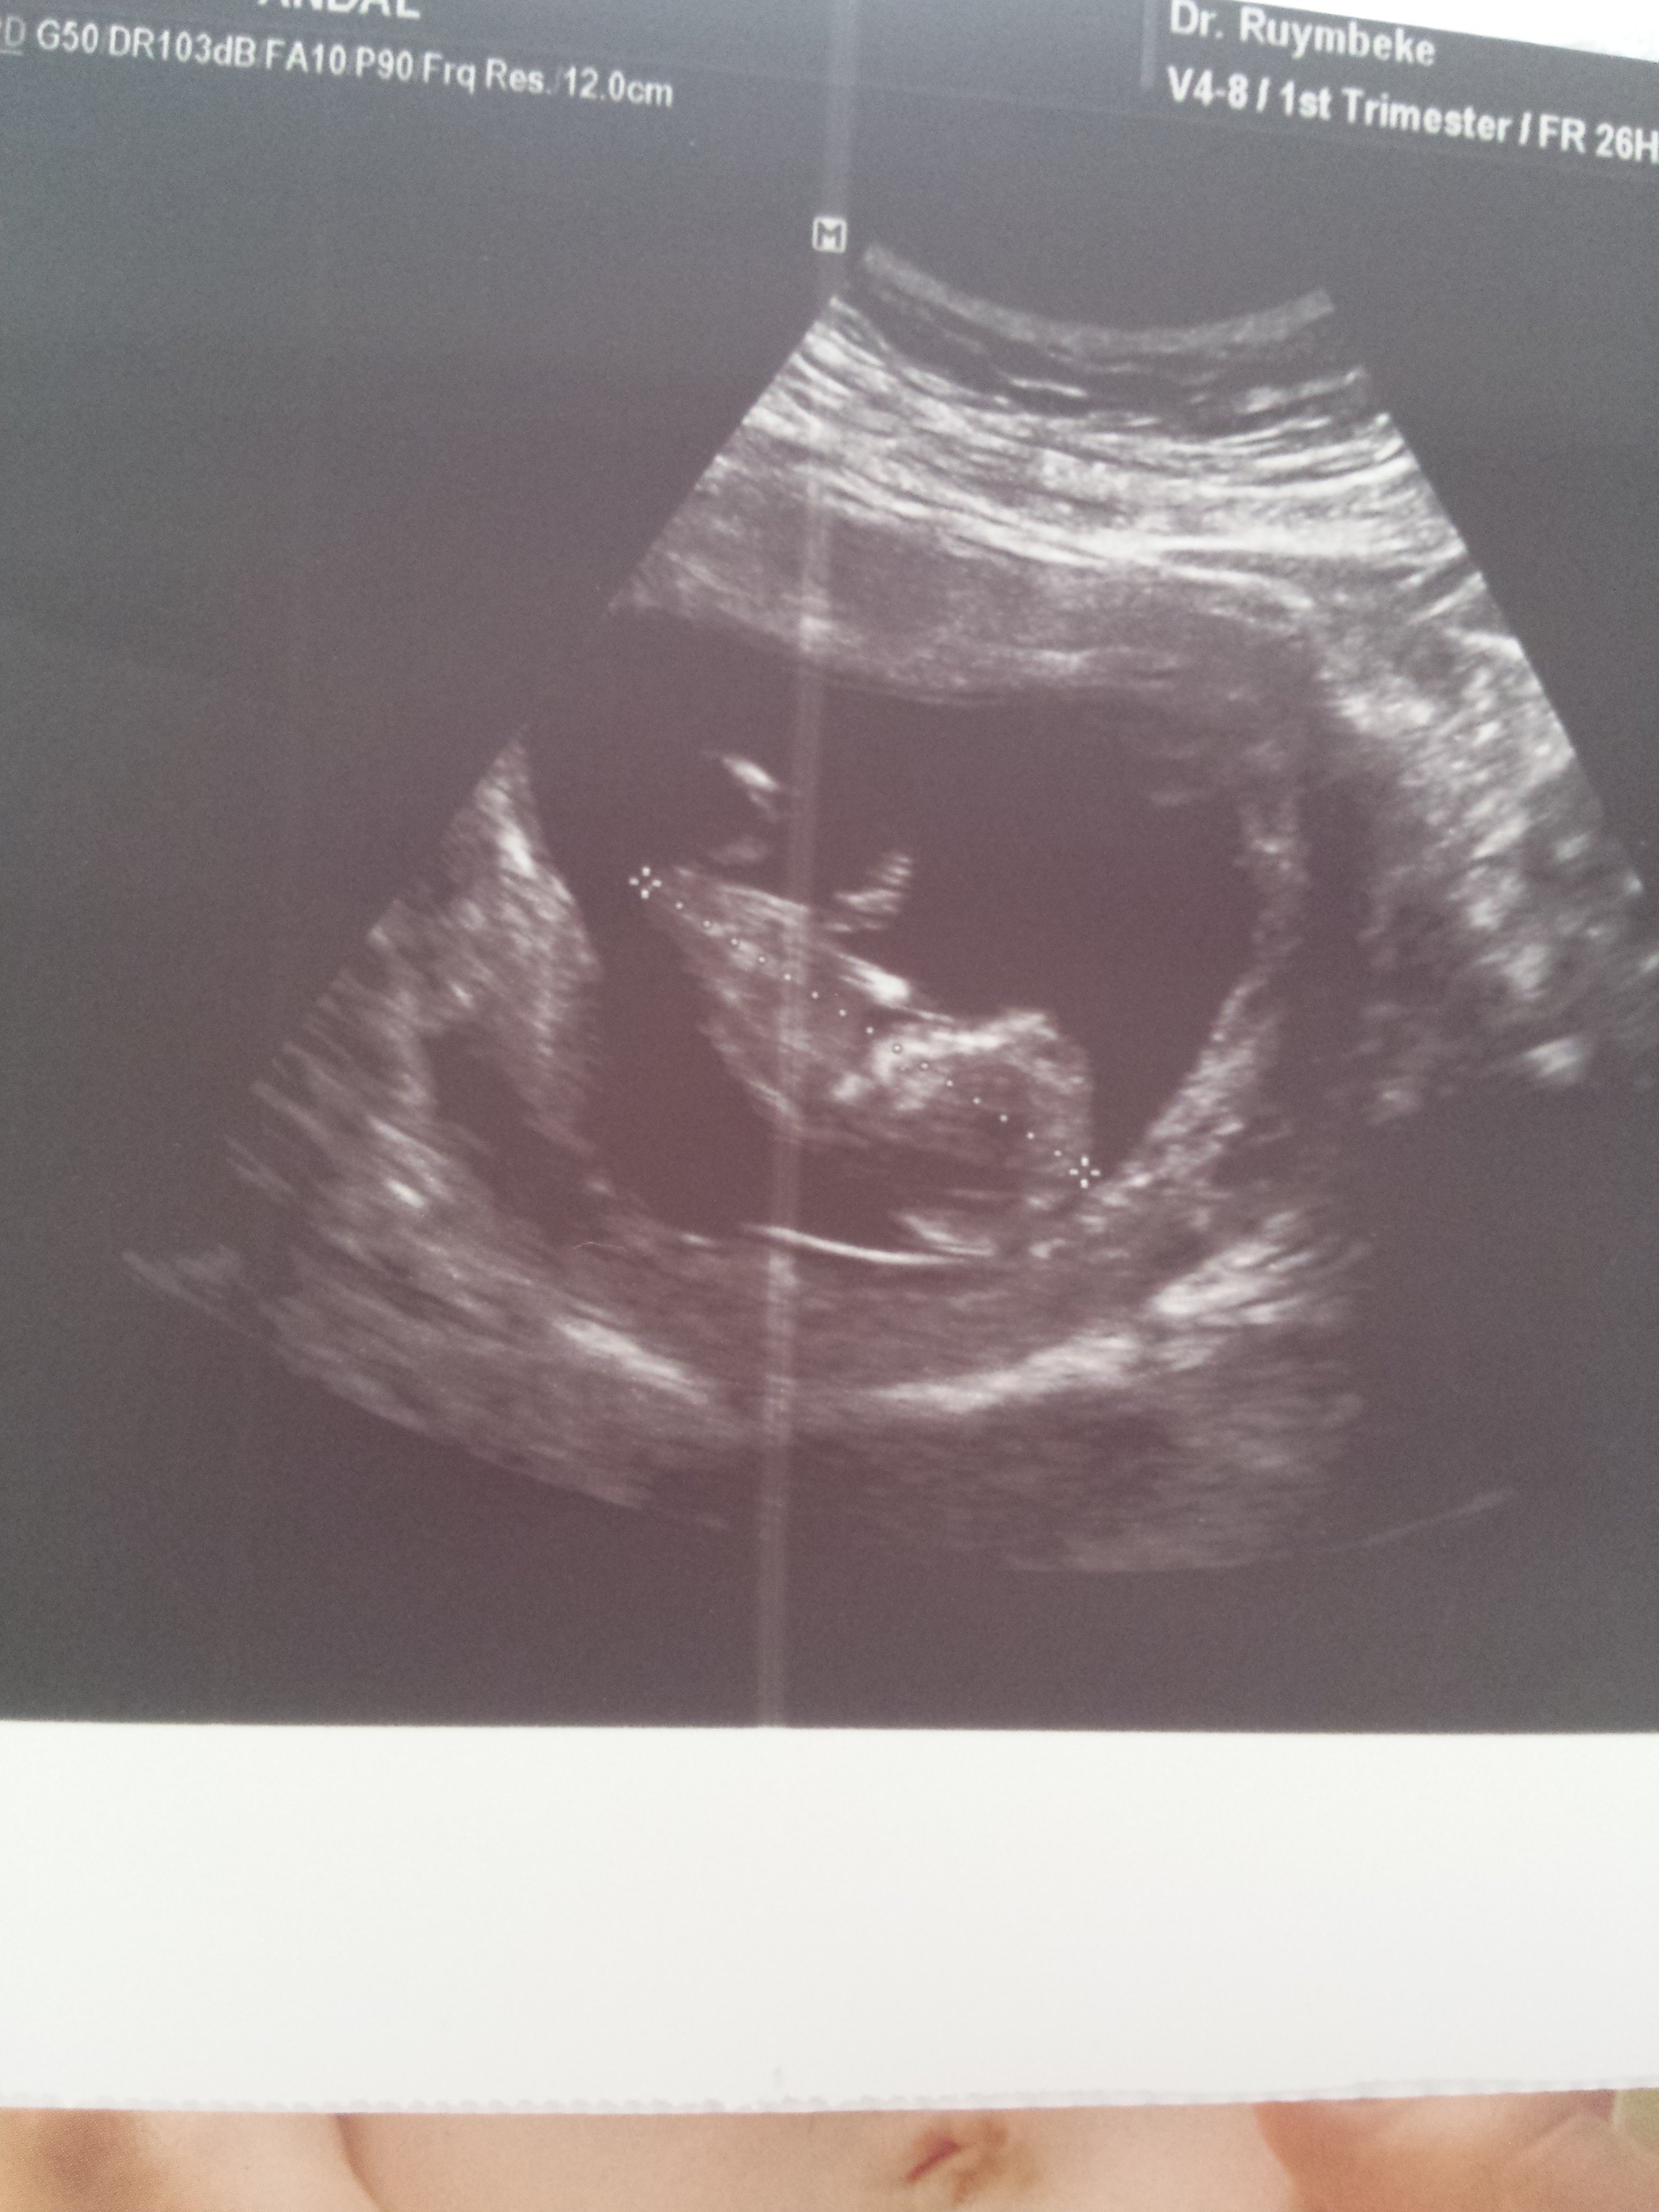

1 1234tmm Yeni Üye Üye 29 Nisan 2017 #264 Ekli dosyayı görüntüle 76263 Ekli dosyayı görüntüle 76264 Ekli dosyayı görüntüle 76264

1 1234tmm Yeni Üye Üye 29 Nisan 2017 #266 Ekli dosyayı görüntüle 76265 11+4 dusuncelerinixi alabilirmiyim *BEYZA*' Alıntı: Yorum yaptığınız yerde fotoğraf yükle butonu var.Yüklemeyi ordan yapıcaksınız. Genişletmek için tıkla ... Cok tesekkur canim sanirim oldu.

Uzman SühaN Administrator 29 Nisan 2017 #267 Merhaba, Nub çıkıntısı pek net değil fakat bebeğinizin cinsiyetinin kız olduğunu düşünüyorum.Sağlıklı gebelik geçirmeniz dileği ile.

Merhaba, Nub çıkıntısı pek net değil fakat bebeğinizin cinsiyetinin kız olduğunu düşünüyorum.Sağlıklı gebelik geçirmeniz dileği ile.